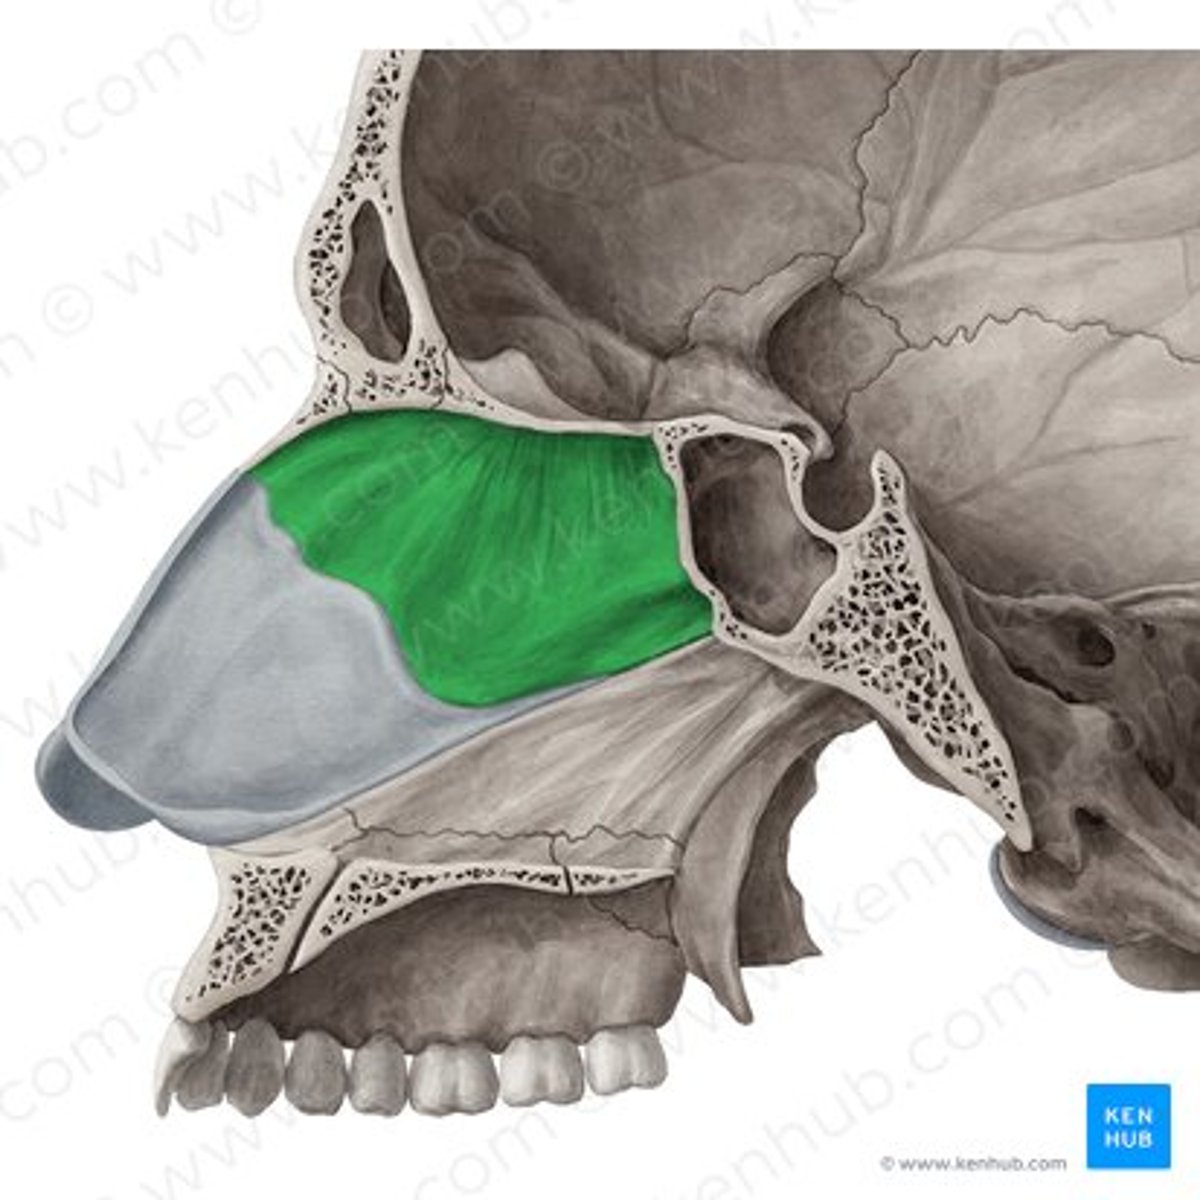

superior meatus

middle meatus

inferior meatus

inferior nasal concha

frontal sinus

nasal septum

hard palate